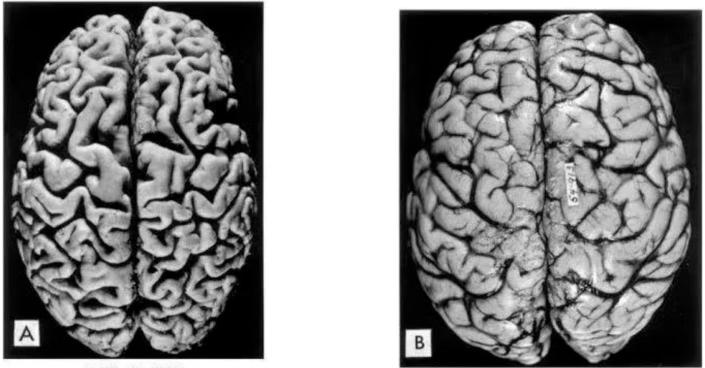

若長期喝酒,就會對大腦記憶產生可察覺的損害,前額葉、海馬體等區域都會收到不同程度的損傷,掃描大腦,能明顯看到海馬體萎縮。

聲明:圖片來源於網絡,與內容無關;如若侵權,請聯繫刪除!